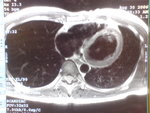

RadioEdric :: 我是白老鼠廿幾號 - 瑪麗醫院新裝之 3T 磁力共振掃瞄器